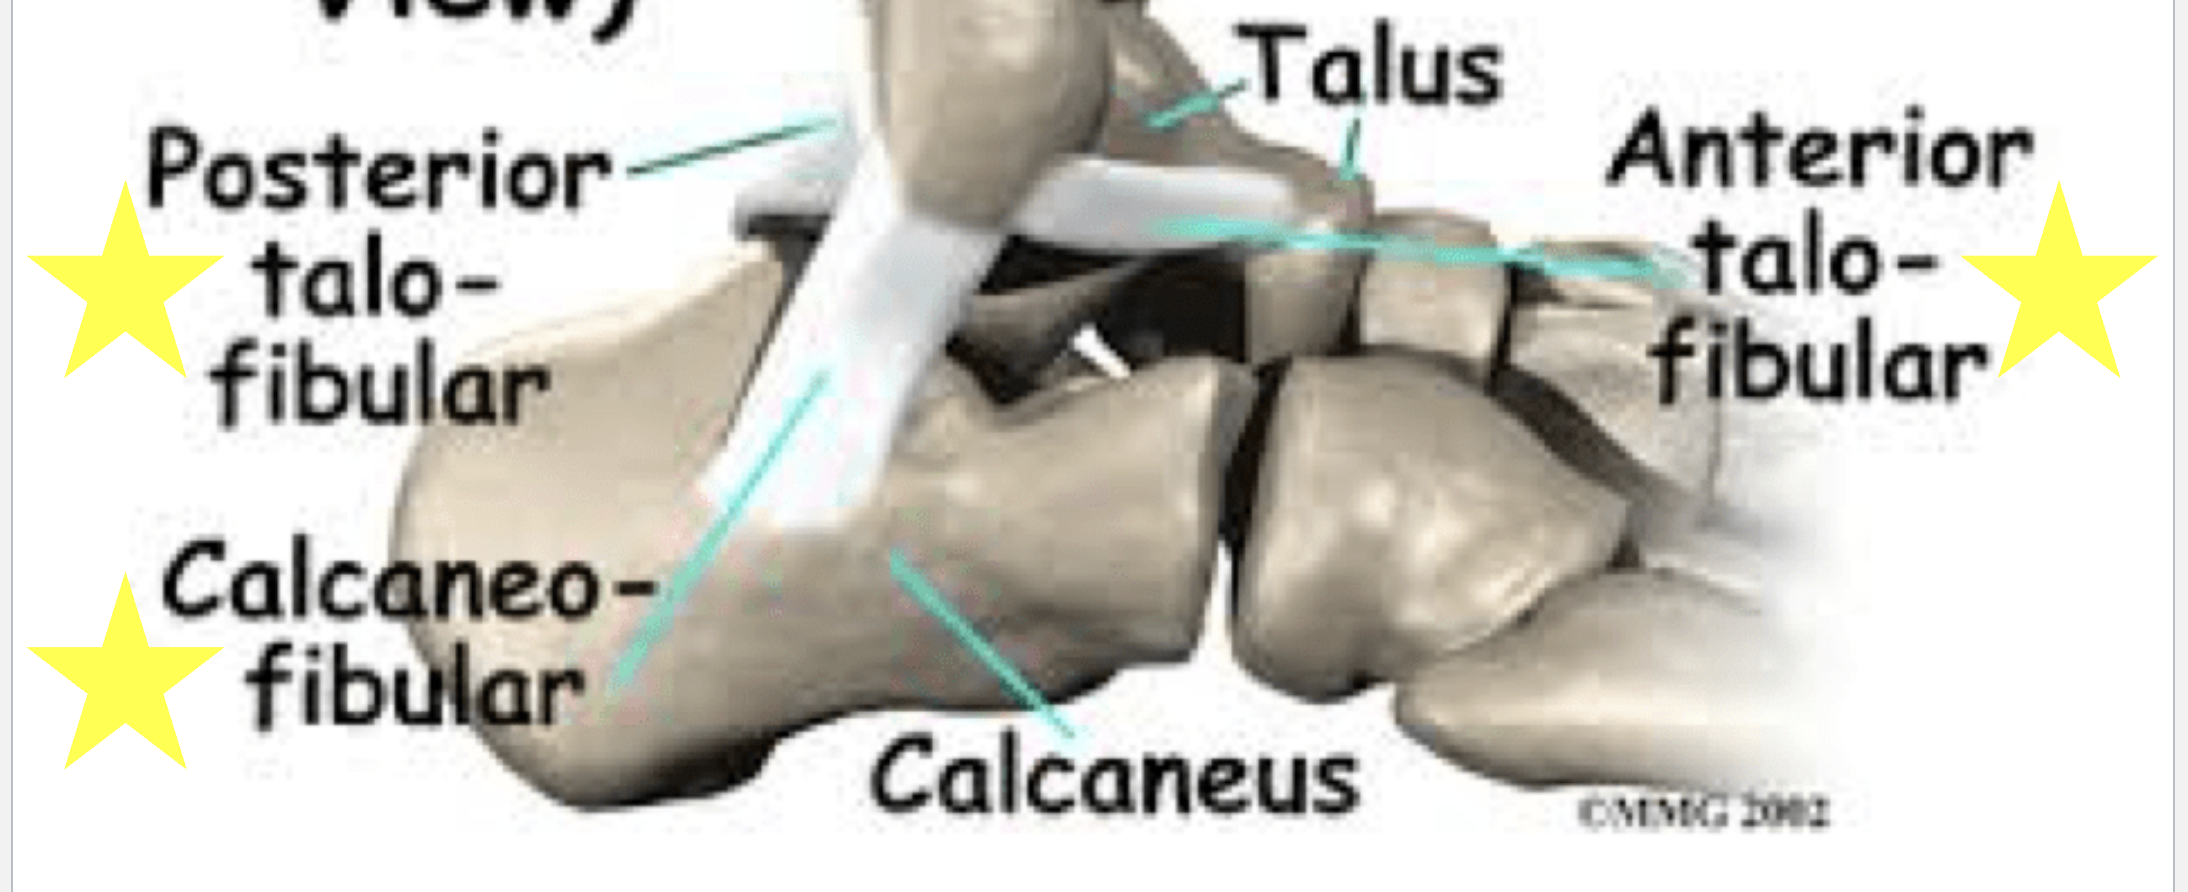

Lateral ligaments

Posterior talofibular, calcaneofibular, anterior talofibular